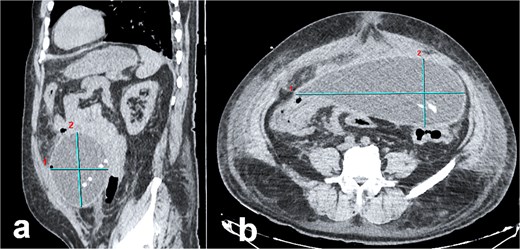

Abdominal computed tomography (CT) demonstrated a large encapsulated cystic mass (9.98 × 12.8 × 23.35 cm) in the abdominal cavity. The lesion adhered to the posterior surface of the anterior abdominal wall, enveloped the dialysis catheter tip, and contained fluid (Fig. 1a and b). Exploratory laparotomy via a midline infraumbilical incision revealed a 20 × 15 cm preperitoneal pseudocyst with dense adhesions to peritoneal tissue and small bowel loops (Fig. 2a and b). The cyst was incised, yielding copious serous fluid, and the entire capsule was excised. The dysfunctional dialysis catheter was concurrently removed. Gross examination identified an irregular peritoneal cyst fragment (14.0 × 18.7 cm) with a pinkish-yellow hue and rubbery consistency, alongside a smaller nodular fragment (4.0 × 3.5 × 2.0 cm). Microscopic analysis revealed adipose tissue with extensive fibrosis and fibroblastic proliferation.

Abdominal CT imaging of peritoneal pseudocyst. (a) Sagittal view: The dialysis catheter tip (arrow) is visualized within the pseudocyst. Note collapsed small bowel loops displaced into the retroperitoneum. (b) Axial view: Encapsulated pseudocyst with thick, enhancing walls (asterisk), and homogeneous serous fluid content. Bowel loops are displaced posteriorly into the retroperitoneum.

The patient’s abdominal CT findings—a large encapsulated cystic mass (9.98 × 12.8 × 23.35 cm) enveloping the dialysis catheter tip—illustrate the sequela of disrupted peritoneal integrity. As described in PD literature, pseudocysts arise from aberrant fluid reabsorption due to adhesions or chronic inflammation, often exacerbated by repeated dialysate instillation [7, 8]. The cyst’s adherence to the anterior abdominal wall and small bowel loops mirrors the propensity of these lesions to form within loculated compartments bounded by peritoneal adhesions [2–7, 9, 10]. Histopathological analysis, revealing fibrous collagenous tissue and fibroblastic proliferation without epithelial lining, corroborates the role of chronic inflammation and macrophage-derived IL-1 in driving fibrogenesis [8]. These findings align with the proposed mechanism whereby recurrent peritoneal insults (e.g. catheter-related infections) incite fibroblast activation and collagen deposition, culminating in cyst wall formation [3, 8].